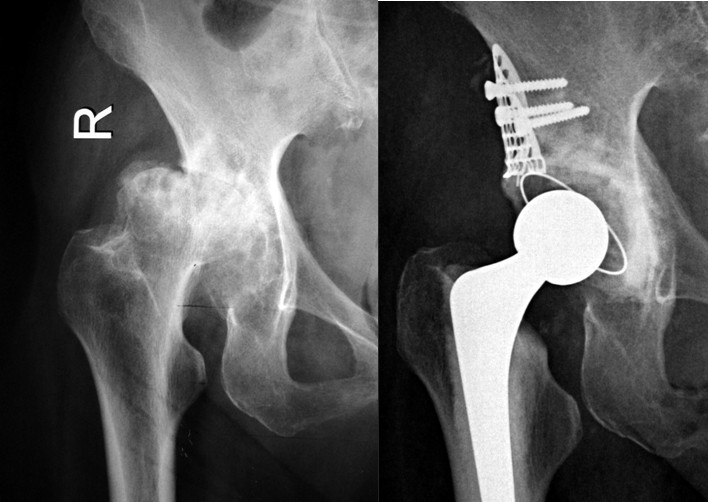

⑴Ⅰ型缺损:髋臼发育不良合并骨性关节炎,髋臼上缘Ⅰ型骨缺损,以金属网包含上缘缺损螺钉固定后,打压植骨,三代骨水泥技术全髋关节置换。

⑶Ⅲ型缺损:右髋关节置换术后骨溶解、假体无菌性松动造成髋臼巨大Ⅲ型骨缺损,行翻修术,以金属网包含髋臼上缘及髋臼内壁后,打压植骨,三代骨水泥技术全髋关节置换。